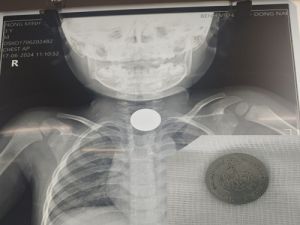

Gắp thành công đồng xu ra khỏi thực quản bệnh nhi

Bệnh viện Nhi đồng Đồng Nai vừa thực hiện thành công ca nội soi gắp đồng xu kim loại có kích thước 20mm ra khỏi thực quản bệnh nhi N.M.T (3 tuổi, ngụ P. Phước Tân – TP. Biên Hòa).